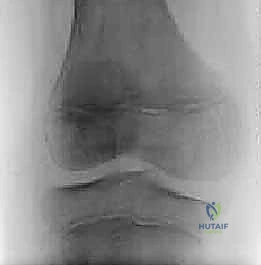

- الأشعة السينية (X-rays): على الرغم من أنها لا تظهر الغضروف، إلا أنها ضرورية لاستبعاد مشاكل العظام الأخرى، وفي حالات الغضروف القرصي قد تظهر اتساعاً في المسافة بين عظمة الفخذ والساق في الجانب الخارجي.